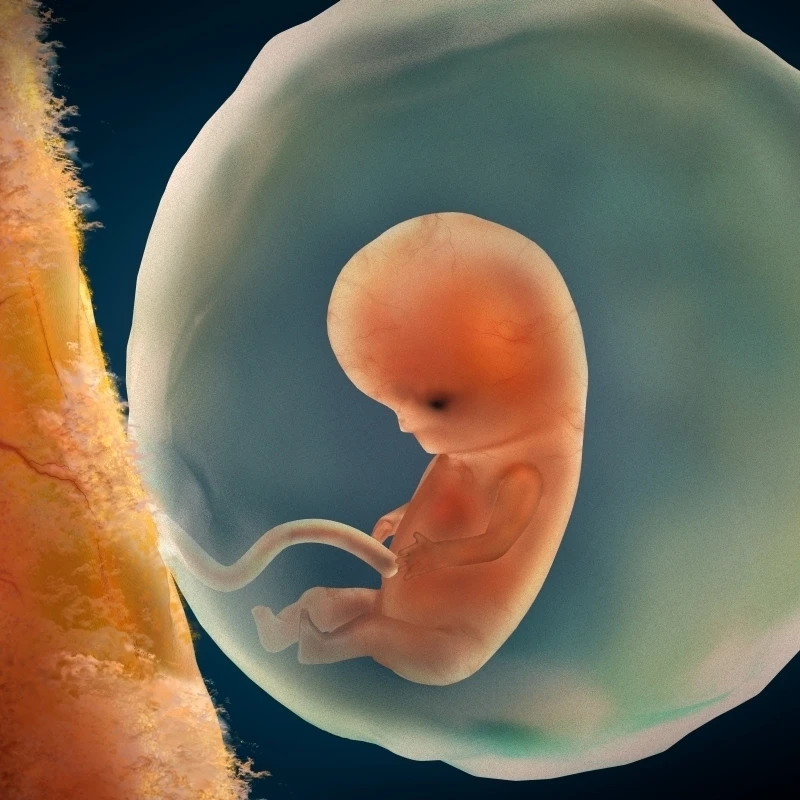

9 Недель Размер Плода Фото⚡ 👉🏻👉🏻👉🏻 ВСЯ ИНФОРМАЦИЯ ДОСТУПНА ЗДЕСЬ, КЛИКАЙ 👈🏻👈🏻👈🏻9 Недель Размер Плода Фото